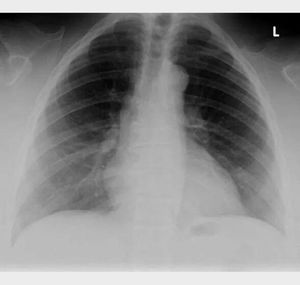

Identify the anatomical abnormality

Cliedocranial dystosis..absence of clavicle of conginataly

Aortic anurysm....? biconvex widening of mediastinum....

Absence of clavicle?

Air under diaphragm

Missing clavicles